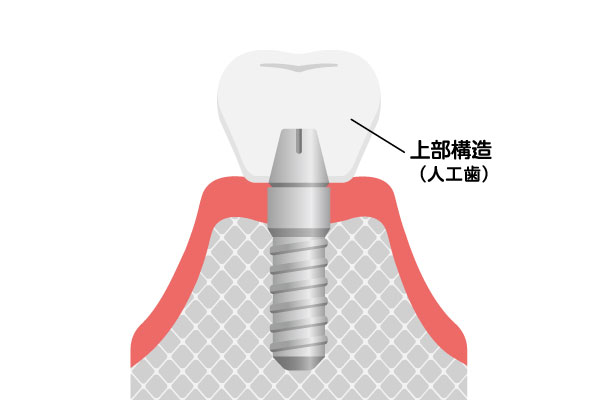

インプラントは、歯を失った部分のあごの骨に、チタンまたはチタン合金製の人工歯根を埋め込み、それを土台として人工の歯を装着する治療です。チタンは、骨としっかり結合する性質があり、生体親和性にも優れた材質です。インプラントは、人工歯根(インプラント体)、土台(アバットメント)、人工歯(上部構造)という3つの構造から成り立っており、審美的に良好なだけではなく、周囲の歯に負担をかけることなく、しっかりと噛む機能を取り戻します。

上部構造(人工歯)

治療完了

インプラントの埋入が完了したら型採りを行い、人工歯(上部構造)を作成します。人工歯を装着し、かみ合わせを調整して治療完了となります。天然歯に近い機能と審美性が回復します。